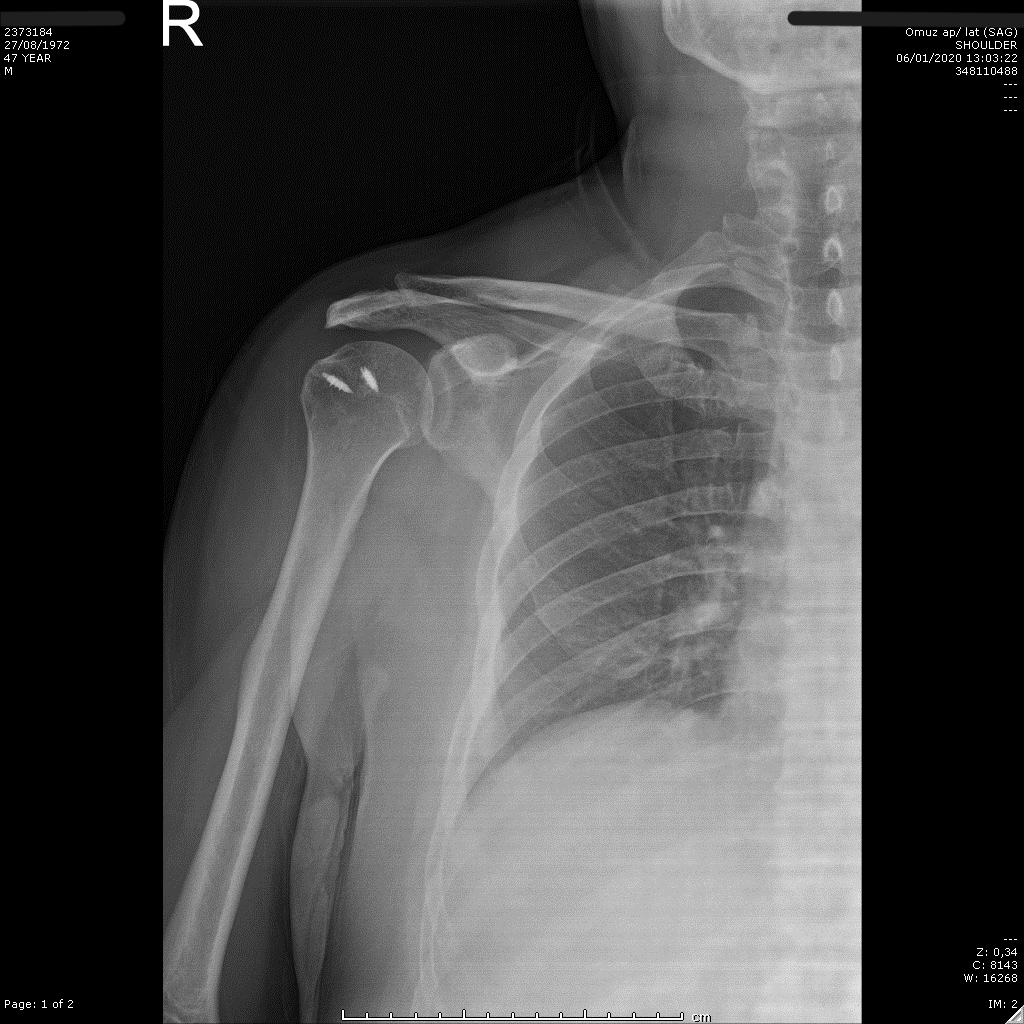

Postoperatif omuz röntgeni — düzelen AHD